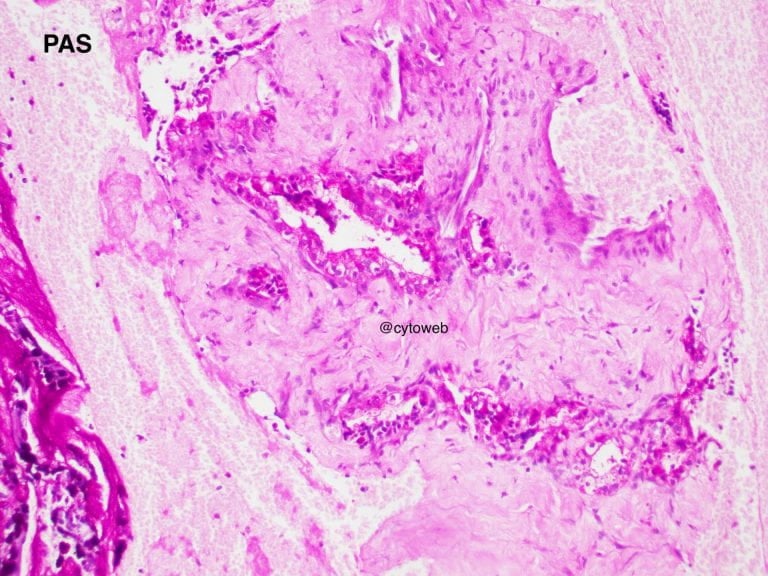

Clinical history: A 50-year-old female was found to have an incidental solitary multi-septated cyst in the pancreatic neck. There was enhancement of the septa of the cyst on CT imaging. Endoscopic ultrasound showed an echogenic central area. The cyst does not communicate with the pancreatic ductal system. Fine needle aspiration of the lesion was performed and 1ml of clear watery fluid was aspirated.